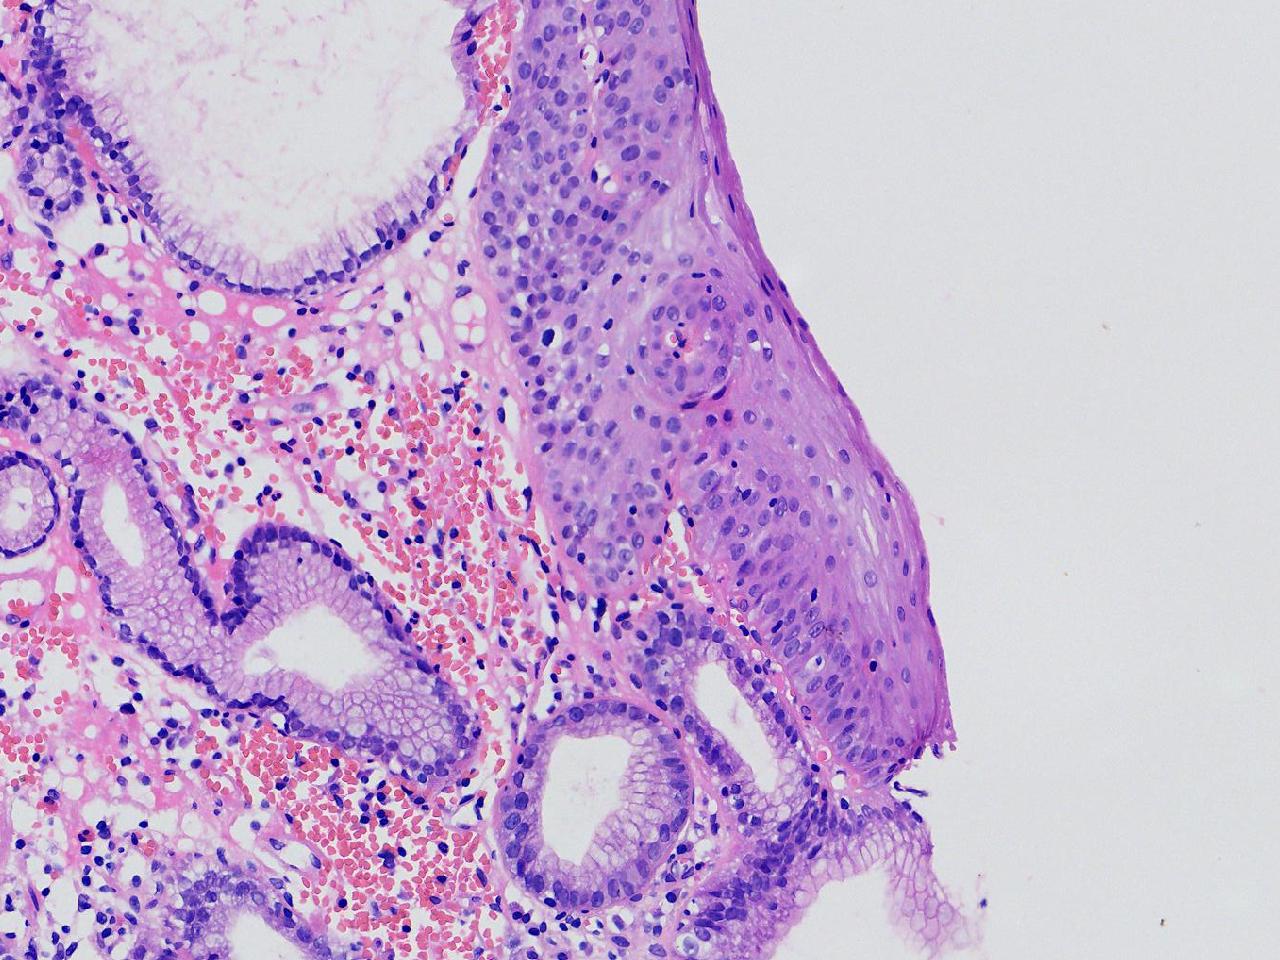

女,38岁,食管距门齿38cm处见一扁平隆起,表面粗糙,活检1块,质软,弹性可。

食管活检

灰白色不整形软组织1块,直径0.2厘米。

结合取材部位排除Barrett食管

粘膜慢性炎。

Barrett食管,粘膜慢性炎。